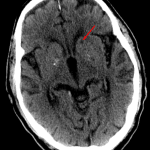

- Age-indeterminate left caudate head lacunar infarct

- Lacunar infarct

Age-indeterminate left caudate head lacunar infarct. Consider MRI for further evaluation.